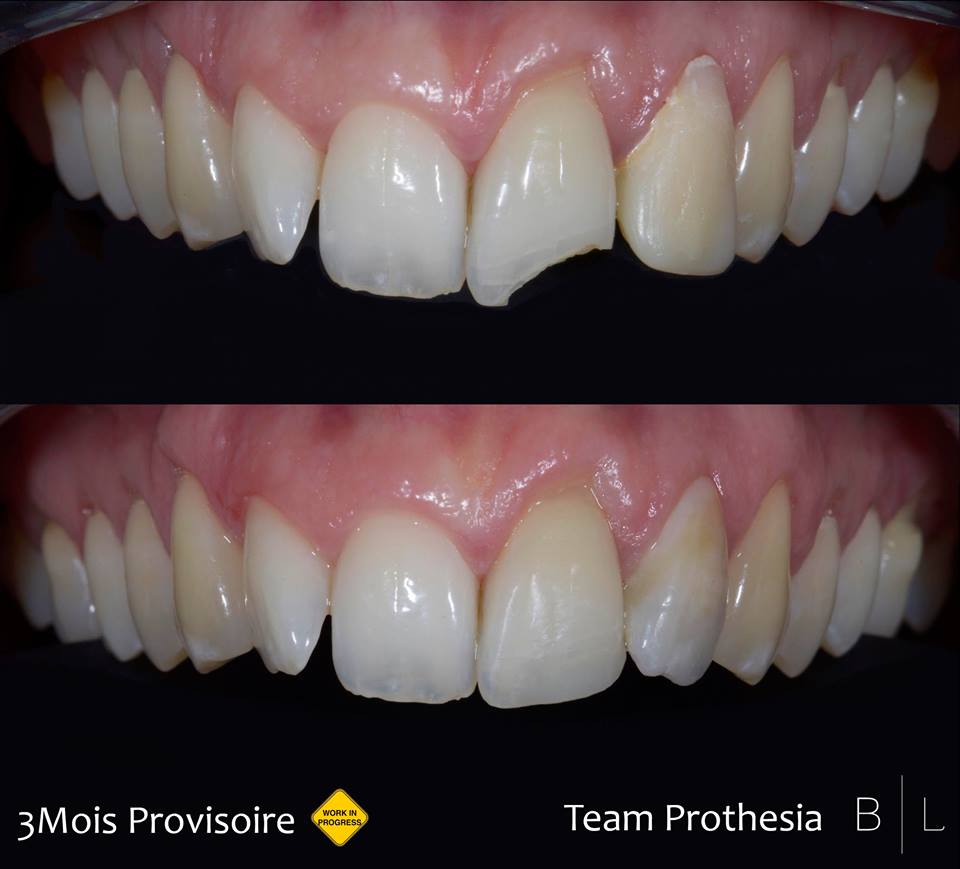

Trauma : prise en charge provisoire en attente pendant 3 mois. Team Prothesia!!

Trauma : prise en charge provisoire en attente pendant 3 mois. Team Prothesia!!